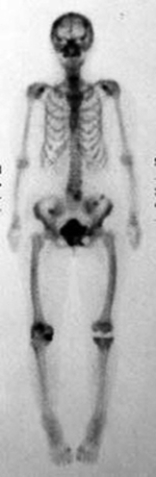

Which of the following imaging techniques illustrated in the pictures would be the most efficient to discover if there is a loose body within a joint?

Q15: Which of the following imaging techniques illustrated

Q17: Which of the following imaging techniques illustrated